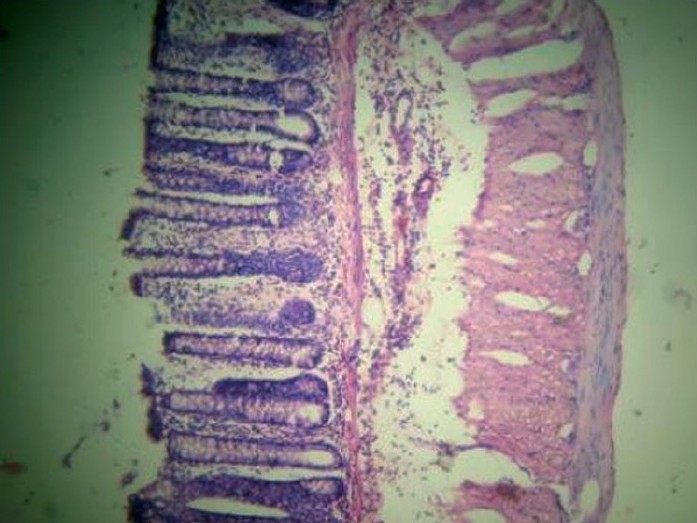

Ethanolic extract of F. vesca (EEFV) fruits showed significant activity against experimentally induced IBD when compared to the experimental control (P < 0.05), with near normalization of colon architecture both macroscopically as well as microscopically [Figure 2]. Tissue oxidative stress was reduced with significant improvement in tissue levels of SOD and CAT (P < 0.05), showing its antioxidant potential, although there was no significant difference in GSH levels when the two groups were compared (P > 0.05). Also, significant improvement in the levels of MPO was observed (P < 0.05) [Table 1].

Figure 2.

Group C (F. vesca): Infiltration up to submucosa, architecture maintained.